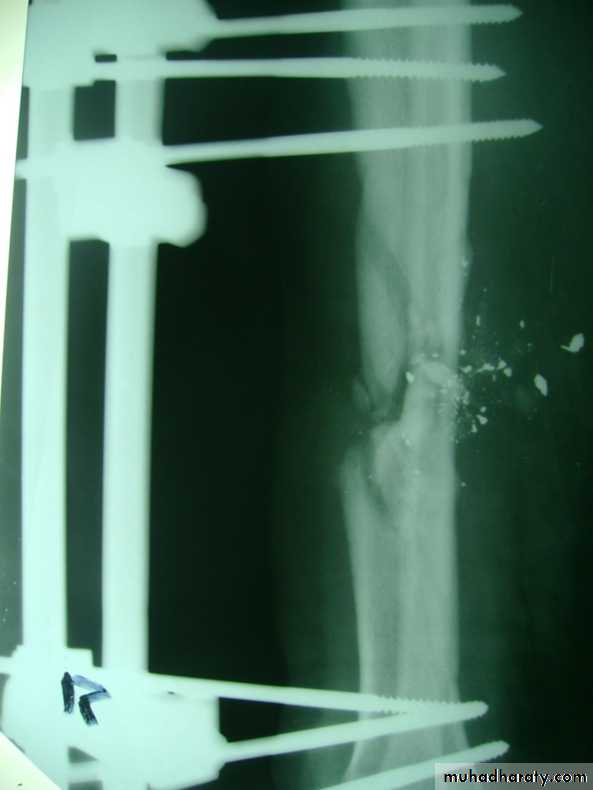

Slide 5Patient with bullet injury to his RT leg1-What is the holding method used. 2-What serious infection might complicate such injury.